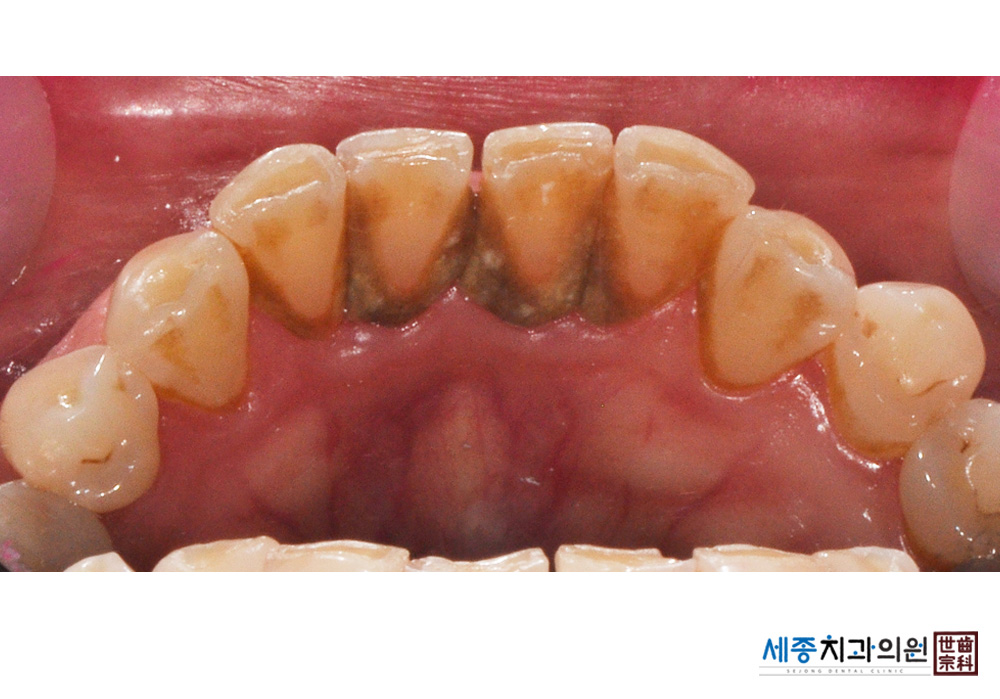

[스케일링] 치주질환 예방 스케일링

치료전 : 2021-03-03

가글마취&저주파 스켈러를 사용한 스케일링